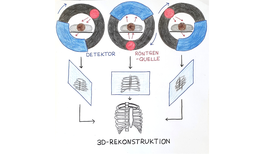

145. Impuls: Computertomographie

Computertomographie (CT) erlaubt es, “Röntgenbilder in 3D” aufzunehmen. Der Computertomograph besteht aus einer Röntgenröhre, die um die zu untersuchende Körperstelle rotiert und aus verschiedenen Sichtwinkeln 2D-Röntgenaufnahmen macht. Ein Computer rekonstruiert aus den vielen 2D-Aufnahmen ein 3D-Bild der untersuchten Gewebestelle. Da viele Röntgenaufnahmen gemacht werden, erzeugt diese Methode jedoch auch eine hohe radioaktive Strahlenlast.mehr...